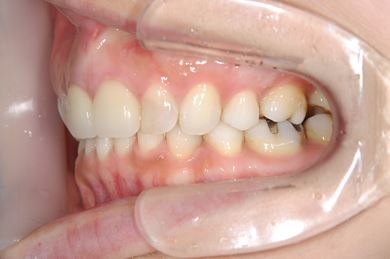

| 主訴 | 歯並び(乱ぐい歯、出っ歯)と歯の色が気になる。 | ||||||||||||||||||||||||||||||||

| 治療方針 | 左上の第一大臼歯がすでに抜歯され欠損の状態で来院されました。デンタルインプラント、あるいはブリッジで補綴するよりも、上あごが突出していること、乱杭歯があることより、矯正治療を第一選択としました。上下第一小臼歯を4本抜歯してその隙間を利用し、治療していきました。抜歯スペースをすべて効率的に利用したいため、上顎左右、下顎左側1本の計3本のインプラントアンカーを使用します。左上は第二大臼歯、智歯を利用しています。今後保定装置の針金は一生装着予定です。上顎の中切歯は左右とも人工的にかぶせものをしています。初診の歯牙変色がなくなり、審美的にもとてもよくなりました。 | ||||||||||||||||||||||||||||||||

| 治療内容 | インプラント矯正(唇側矯正ホワイト、審美ワイヤー、左右上顎第一小臼歯抜歯、上顎インプラントアンカー) | ||||||||||||||||||||||||||||||||